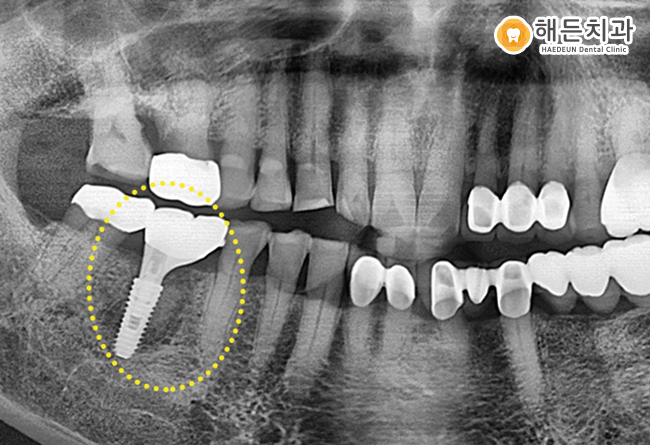

환자분께서 제공을 허락한 사진 중 치료 전에 촬영한 초기 X-Ray 사진인데요. 노란색 점선으로 표시된 치아 아래를 자세히 보시면 다른 곳과 다르게 검은색으로 빈 공간처럼 생긴 부분이 보이실 겁니다. 해당 부분은 치근에 염증이 생겨, 잇몸뼈가 녹아 검게 보이는 것인데요.

만일 뿌리 부근에 염증이나 고름이 있는 경우 심한 통증을 느낄 수 있고 출혈이 자주 나타나게 됩니다. 심한 경우에는 치아까지 흔들릴 수 있습니다.